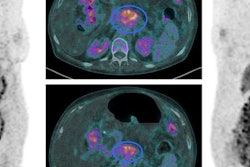

When you see a peripancreatic collection, then describe where it is and outline its characteristics in detail. Clinical images courtesy of Dr. Thomas Bollen."The day-one scan fooled the clinicians big time. This is often the case. We should only perform a CT scan when we suspect a patient of having a severe complication, such as bowel ischemia, or if there is diagnostic uncertainty," Bollen emphasized. "If a patient cannot tell you that they have abdominal pain because they are unconscious, but they have elevated enzymes, then they need a CT to confirm the diagnosis."

"In acute pancreatitis, describe what you see, rather than jumping to conclusions," Bollen said. "If you see nonenhancement areas, then describe the location and extent, and if you see a peripancreatic collection then describe where it is and its characteristics in detail."